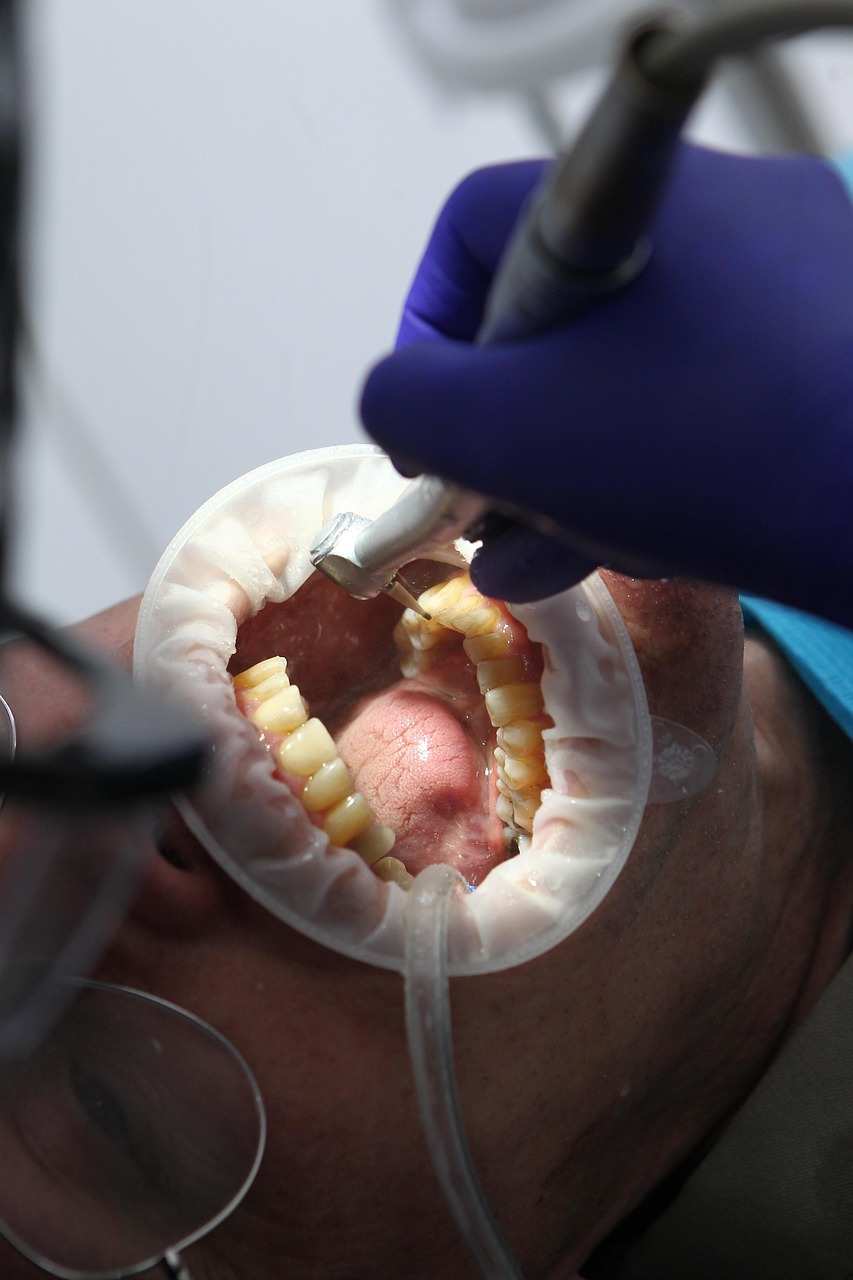

📷 사진 펼쳐보기 / 접기